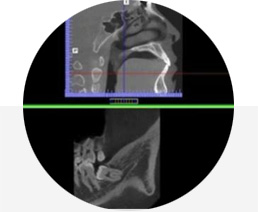

计算机辅助计算结合3D数字化体验,可以精准控制牙齿的移动及咬合调整,完美还原牙齿形态、牙列特点及咬合情况(单颌80-100万数据点);结合CBCT,更可以还原牙根情况,确保安全。

首次突破CBCT真实牙根技术,不仅排齐牙冠更排齐牙根,做到真正的“牙齿”排齐。结合患者骨皮质边界模拟技术,将牙根排列于牙槽骨中心,从而降低正畸复发概率,减小正畸风险。